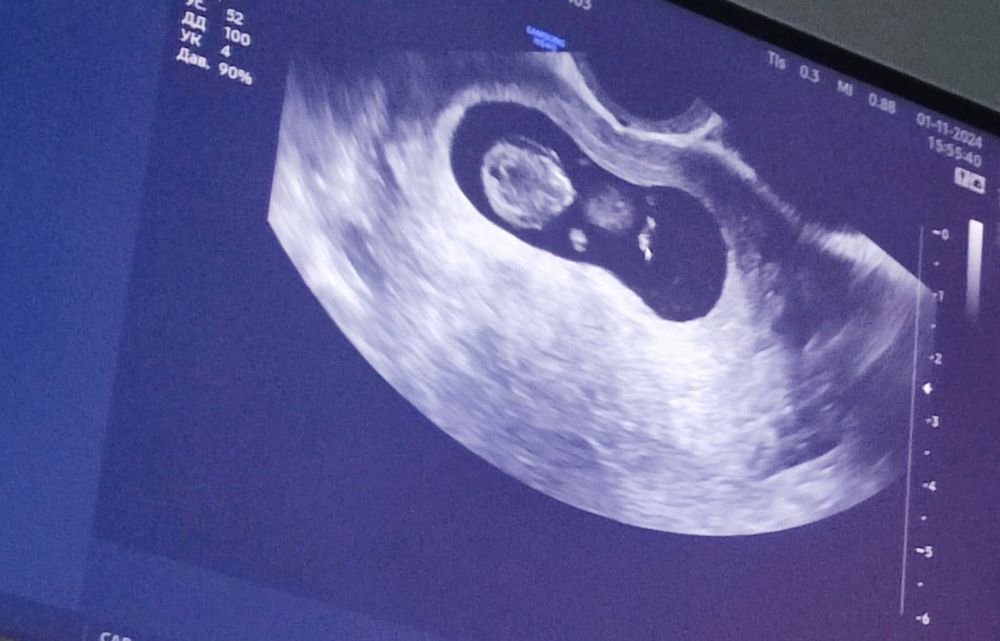

Дарина в Зачатие год Покидайте фото узи в 9 недель 🙏🏻 УЗИ Девочки у кого остались или есть фоточки покидайте пожалуйста! Хочу сходить в 9 неделек на узи, с монитором, хочется узнать как что там примерно видно будет Посмотрите еще 20 записей на эту тему Лучший ответ Елена 9н 2д двойня 02.11.2024 Ответить Отменить Ответить Таня Орозова 01.11.2024 Ответить Екатерина 01.11.2024 Ответить Екатерина Екатерина, чуть больше, 9,5 01.11.2024 Ответить Евгения 9+3 недели 01.11.2024 Ответить ЛисАлис 01.11.2024 Ответить Екатерина 01.11.2024 Ответить Екатерина Екатерина, 9 недель ровно, первое УЗИ 01.11.2024 Ответить Екатерина Екатерина, ножки попка к верху 😄 01.11.2024 Ответить Дарья 01.11.2024 Ответить Евгения Дарья , а вам делали трансвагинально или абдоминально? 01.11.2024 Ответить Дарья Евгения, трансвагинально . А вот 10 недель узи) 01.11.2024 Ответить Евгения Дарья , ух ты) а мне абдоминально делали😁 как в этот раз будут не знаю, пойду в другое место 01.11.2024 Ответить Евгения 01.11.2024 Ответить Мира В интернете нашла)) 01.11.2024 Ответить Девочки подскажите !! Пост нытья Чаты Беременных Выберите чат: Январята-2026 Февралята-2026 Мартята-2026 Апрелята-2026 Майчата-2026 Июнята-2026 Июлята-2026 Августята-2026